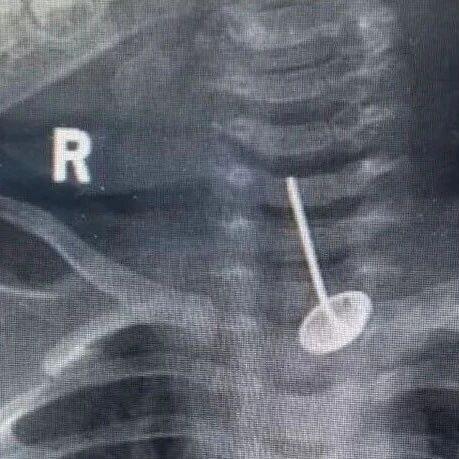

此外,南宁市妇幼保健院新生儿科主任医师曾贵祥表示:“我们的脑袋就像一个硬壳一样,里面脑子是软的。如果你这样晃动,轻的话可能会导致蛛网膜下腔出血,或者是硬膜外出血,如果晃动幅度再大一点的话,可能让脑实质出血。”还可能造成颈椎脱位,更会增加患上摇晃婴儿综合征的风险,严重时可导致癫痫、智力障碍、肢体瘫痪甚至死亡,且损伤多为不可逆。